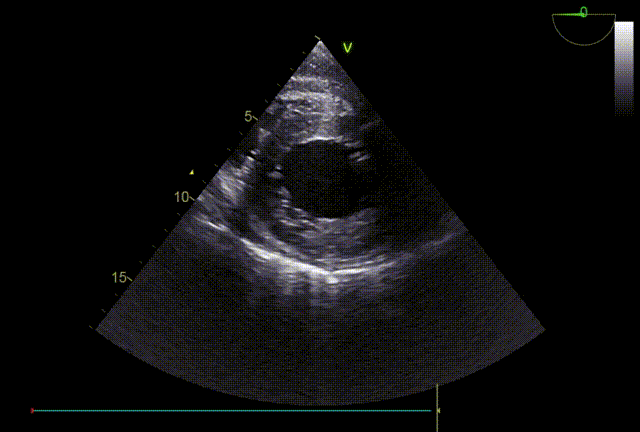

TTE入院

TTE